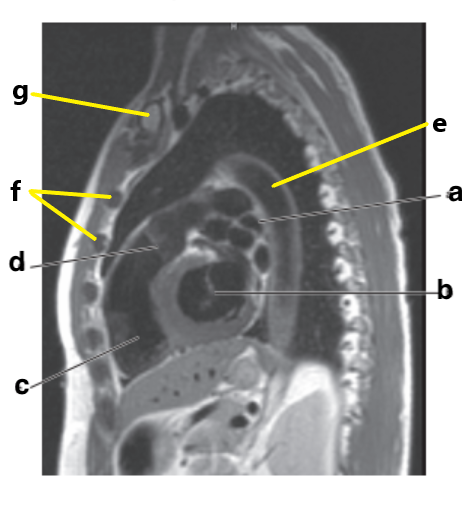

What is letter b?

Left ventricle

Which letter is the ascending aorta?

f

What is letter c?

Aortic arch

What is letter f?

Abdominal aorta

Ascending aorta

Descending aorta

Interventricular septum

Basilar artery